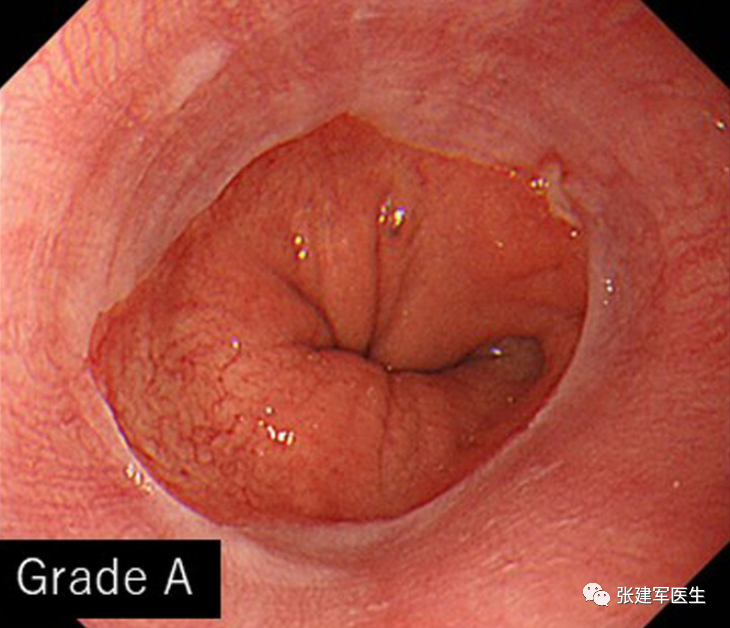

胃十二指肠镜检查

能直观评估食管、胃以及十二指肠粘膜状态,诊断糜烂性食管炎及巴雷特食管(Barrett's esophagus),明确食管裂孔疝的大小及类型,确定食管裂孔疝有无扭转。